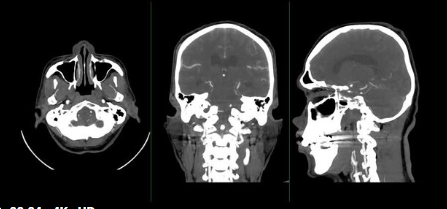

뇌출혈 후유증은 뇌 영상 검사(CT, MRI), 신경학적 검사, 인지 기능 검사, 언어 평가 등을 통해 진단합니다.